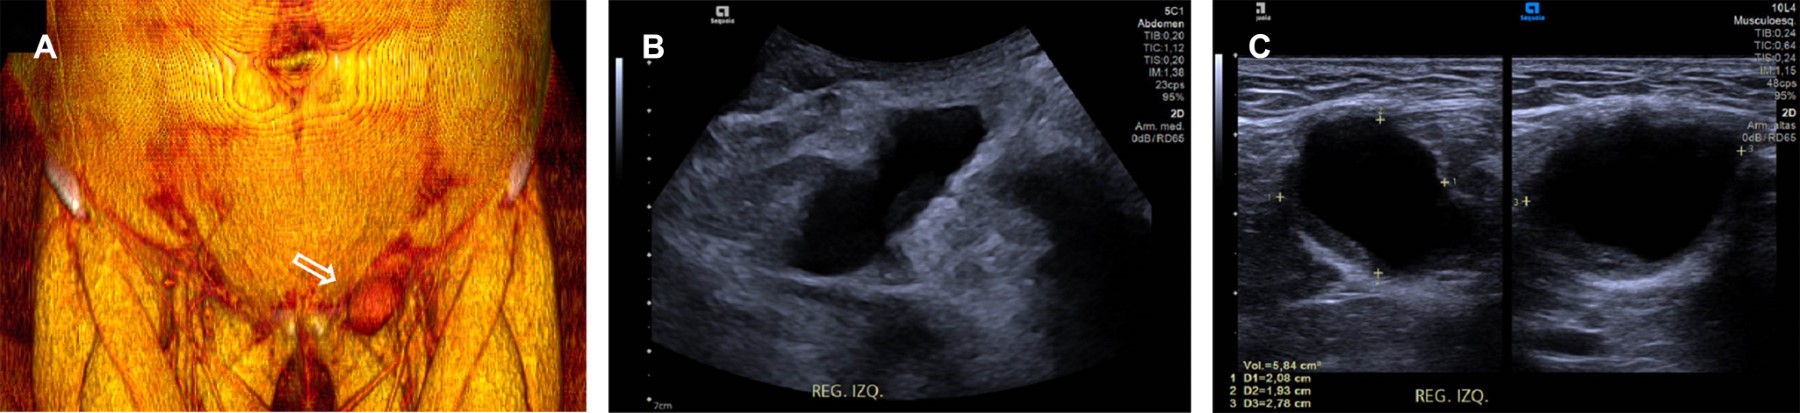

Figure 2